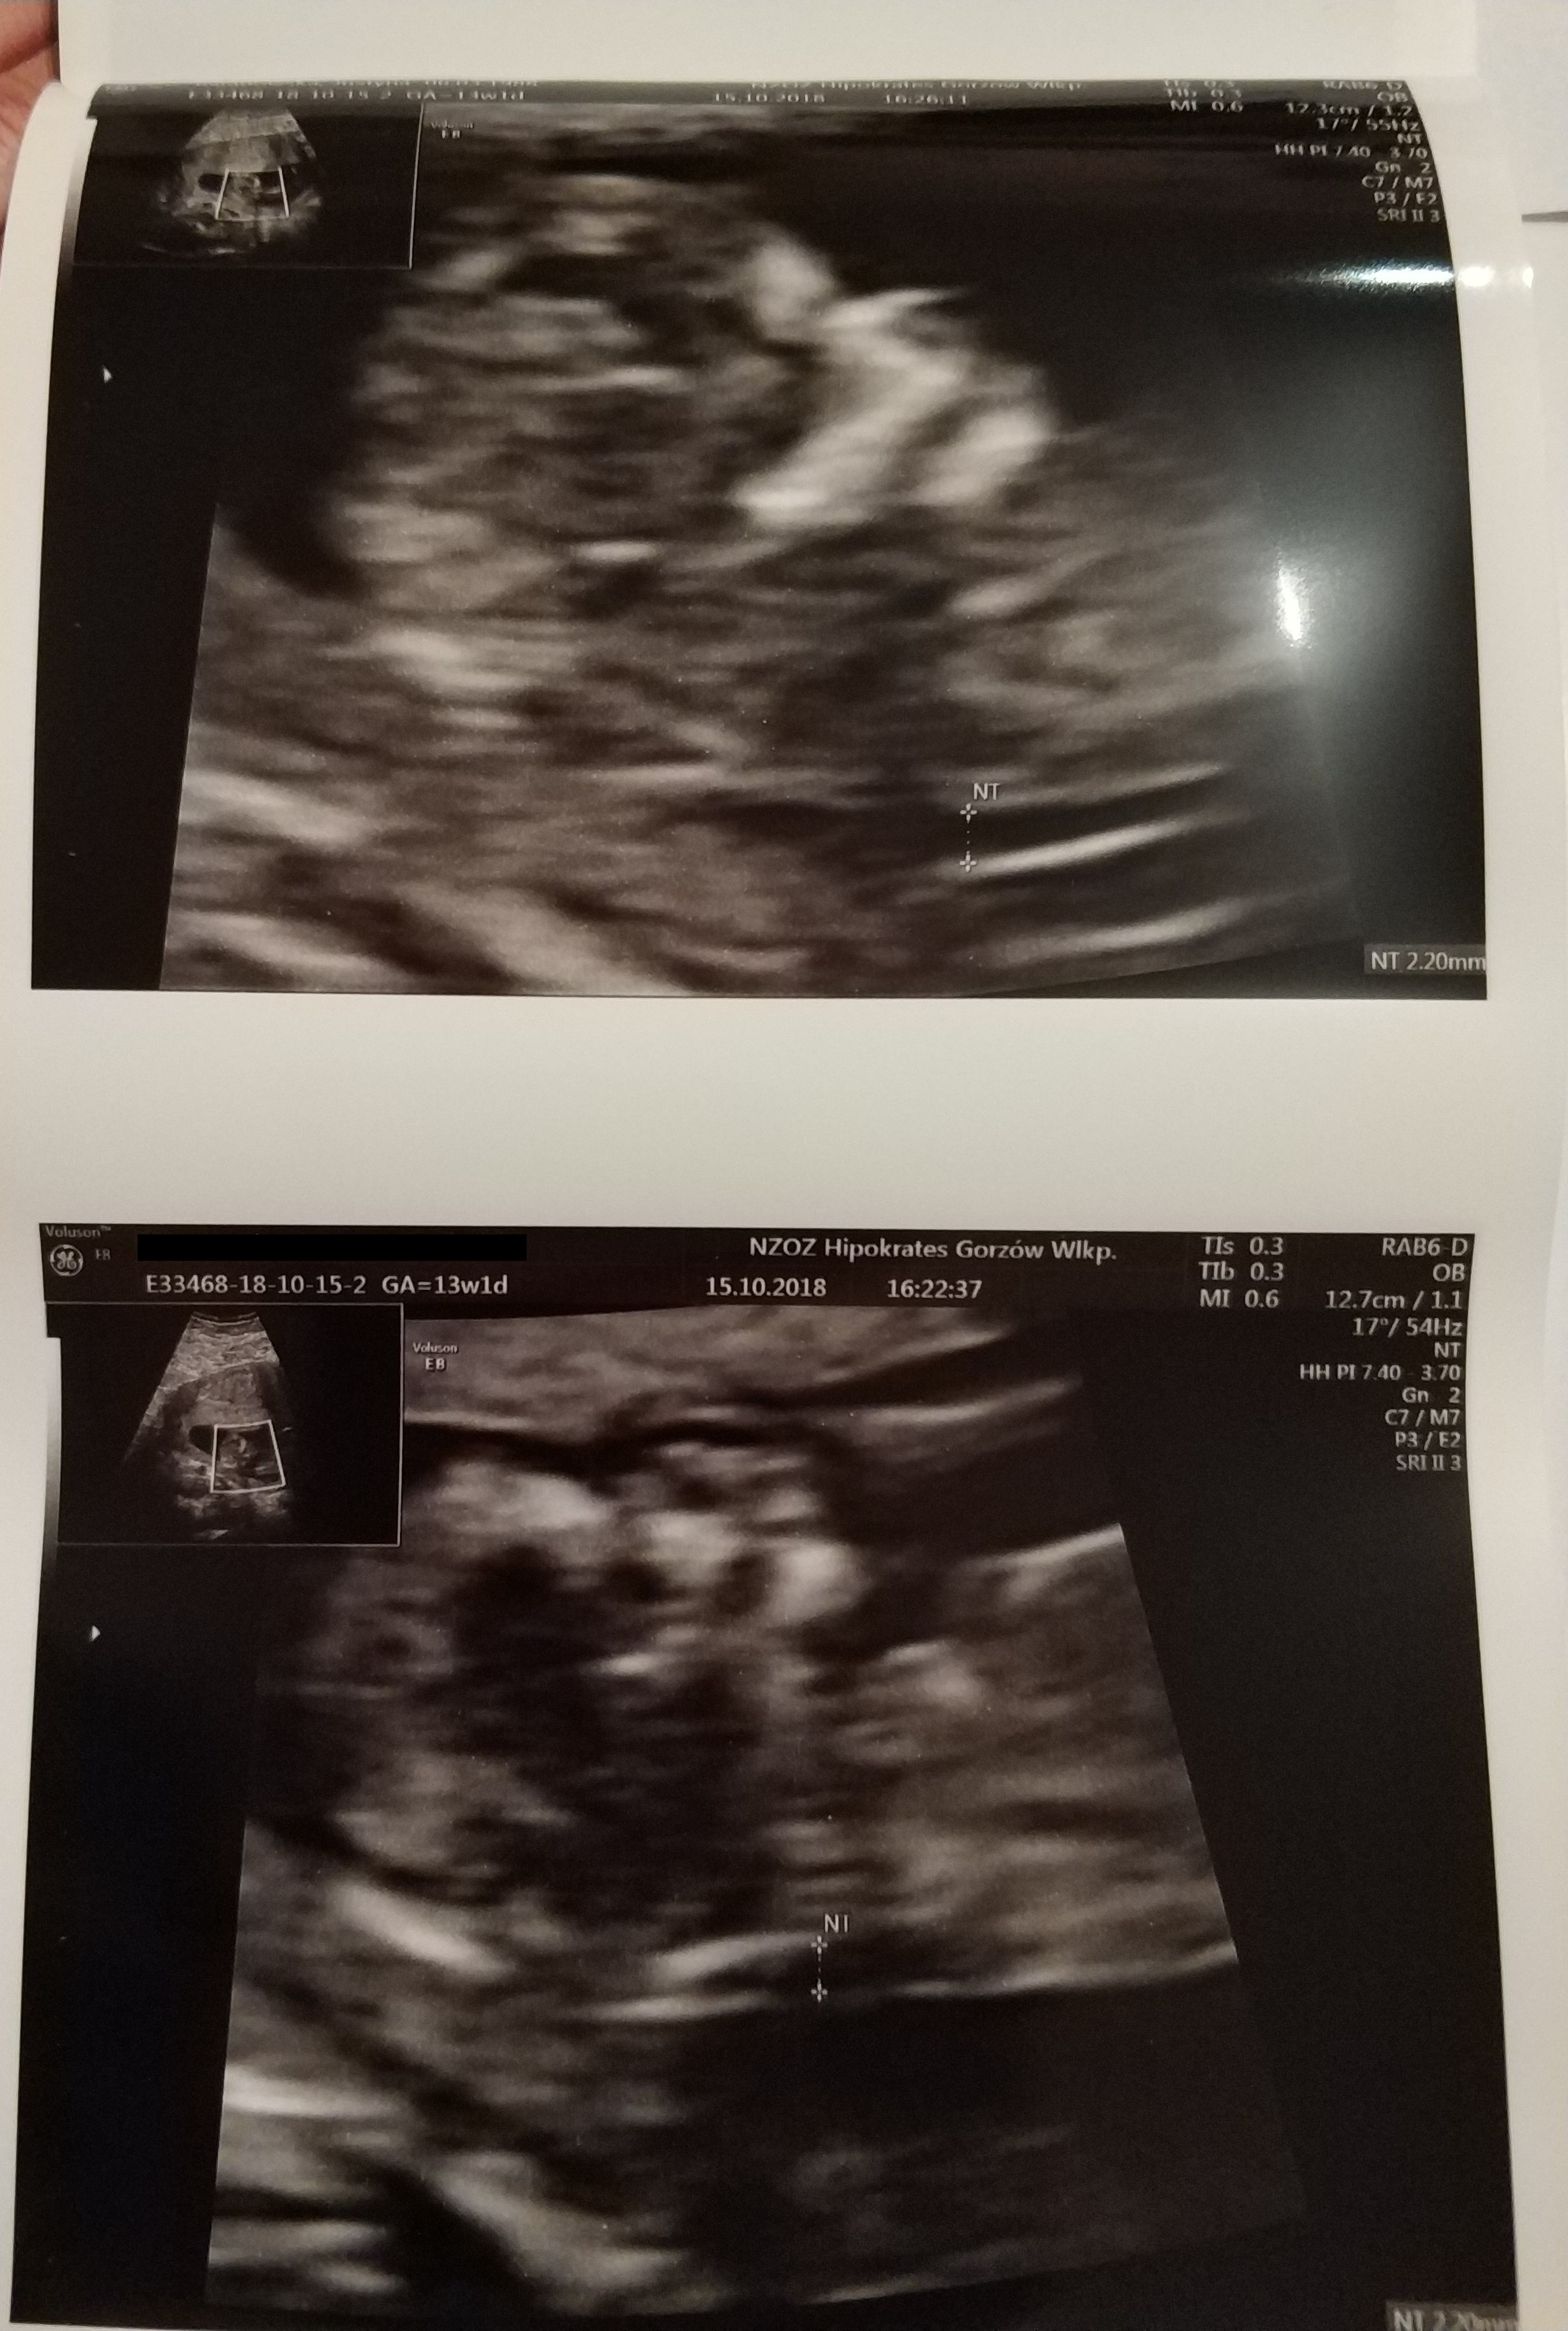

Moje prenatalne wwyszly prawidlowo. dzidzia ma 63mm, odpowiada 12+5, glowka w normie wielkoscia jak z OM 13+1.

serduszko 160u/min w koncu moglam uslyszec!! :)

pecherzyk ciazowy: owalny , NT: 2,2

zarys tułowia: prawidlowy, kosc nosowa: widoczna. Termin porodu 21 kwietnia.

obraz "motyla" mózgu prawidlowy, powloki jamy brzusznej ciagle, cewa nerwowa szczelna, spektrum przeplywu przez zastawkę trojdzielna i przewod zylny - nie do oceny. no i tutaj musze wam powiedziec masa wzruszen byla. dzidzioł tak fikal krecil sie i skakal ze nie szlo go badac. musialam sie obkrecac, kaszlec prowokowac czorta malego.. Pani dr stwierdzila ze niezly skoczek zamieszkuje.

No i prawdopodobnie synek ale mowila zeby jeszcze spokojnie podchodzic do tego.

jestem zadowolona z badania Pani ladnie tlumaczyla, monitor swoj mialam nad glową i wszystko moglam sledzic.

zalaczam kilka fotek :)